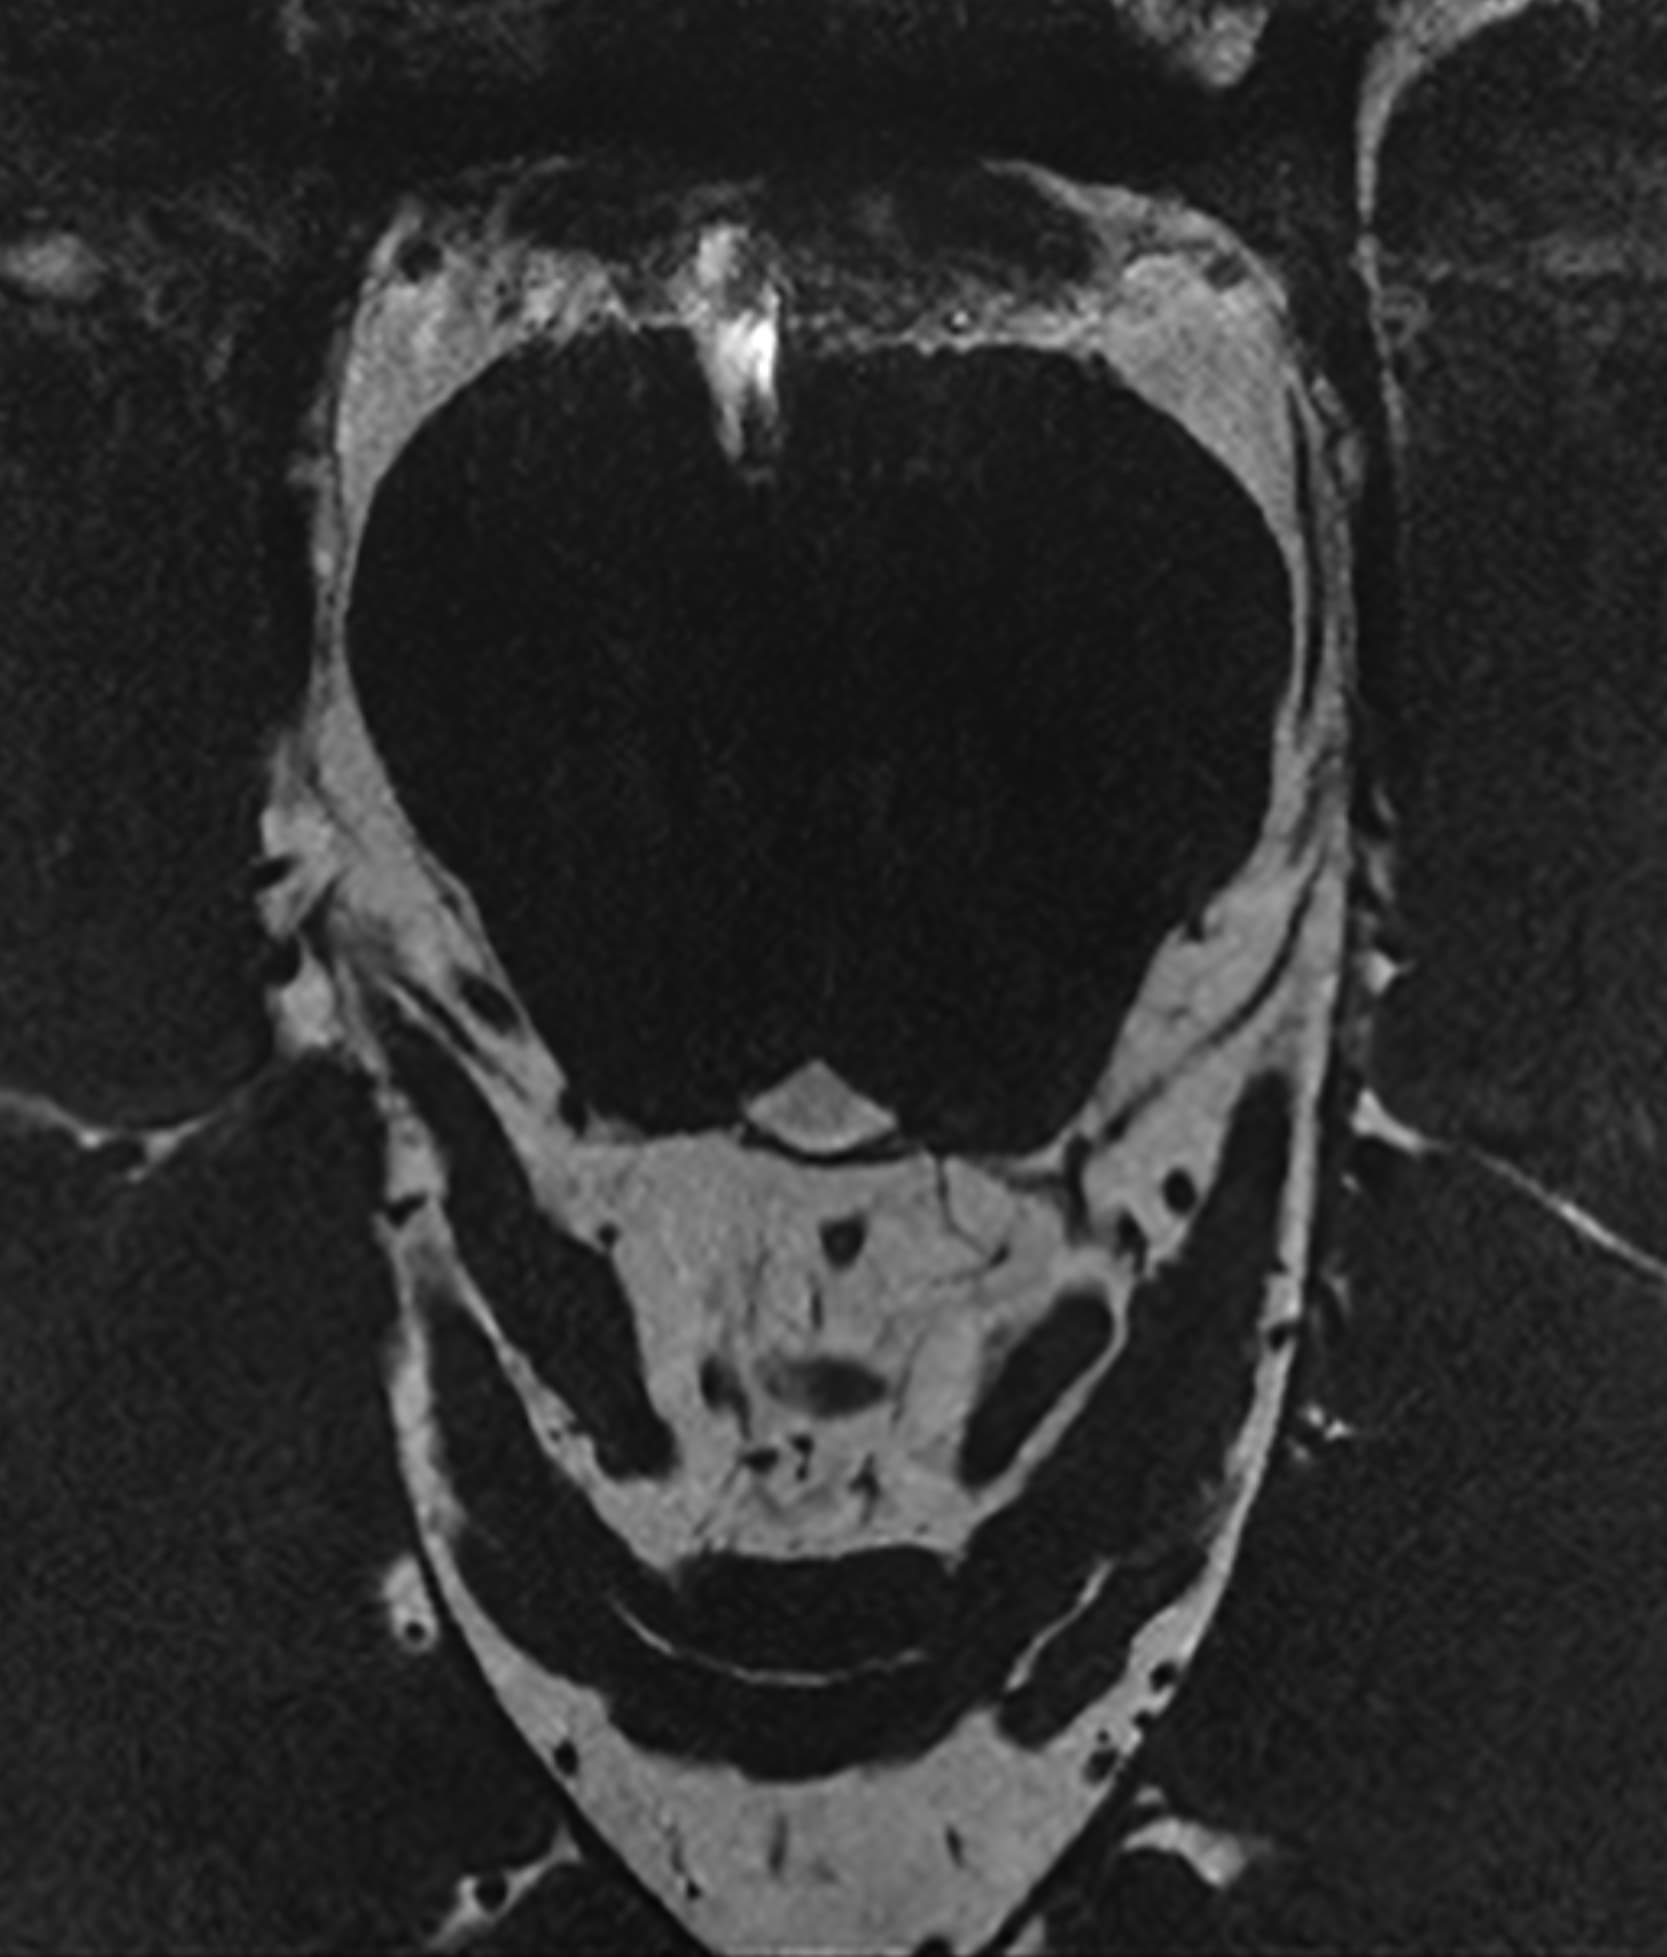

Δείτε πραγματικά παραδείγματα του SwiftMR™ σε διάφορα συστήματα MRI και ανατομικές περιοχές

Scan time 03:14

Scan time 02:07